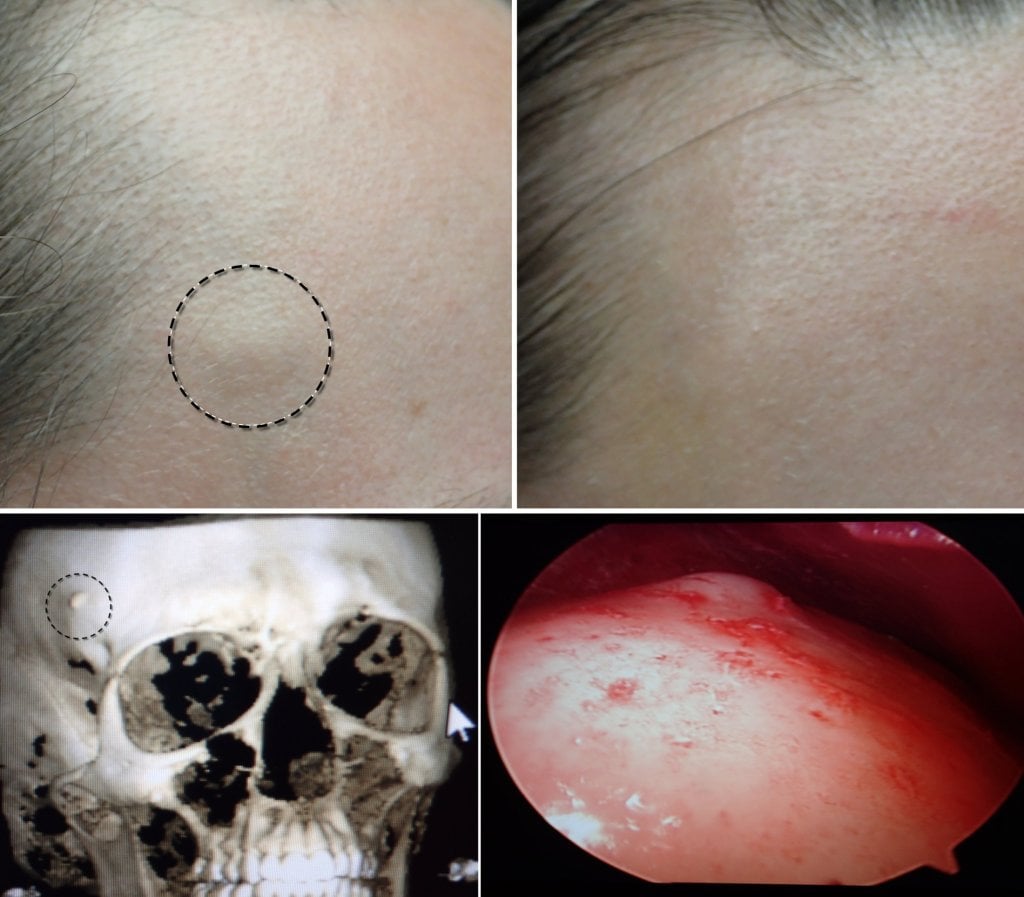

The CT scans below shows a typical forehead osteomas from the side and transverse views. The CT is performed to verify that the lesion is in fact a benign osteoma and not some other lesion that may communicate with deeper structures.

The images below show selected before and after cases of endoscopic osteoma removal.